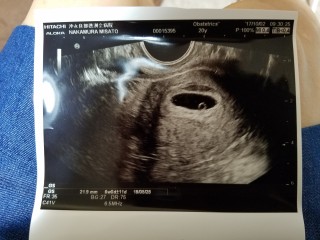

胎嚢が小さくて不安でたまらない方へ。 5w0d時のエコー写真です。 5wで胎嚢3ミリ…先生からは何も言われなかったものの、小さくてとても不安で検索魔になっていました。 しかし目に入ってくるのは良くない結果だったという情報ばかり。 前回、稽留流産を経験していたためとてもナーバスになっていました。 2週間後の検診までが長くて長くて…。 でもちゃんと育っていてくれました! 現在は10週で順調に成長しています。 どうか今不安でいるお母さん、お腹の中の子供の生命力を信じてあげて下さい。

今日で5週☆8.5ミリ☆ 前回は流産してしまったので安定感までは不安だけど、頑張ってほしい! 2週間後に絶対心拍確認できますように。 神さまお願いします。